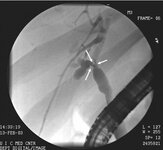

Imagem de colangiopancreatografia retrógrada endoscópica (CPRE) de colangiocarcinoma do ducto hepático com estenose do ducto (setas)

Do acervo de Dr. Joseph Espat; usado com permissão